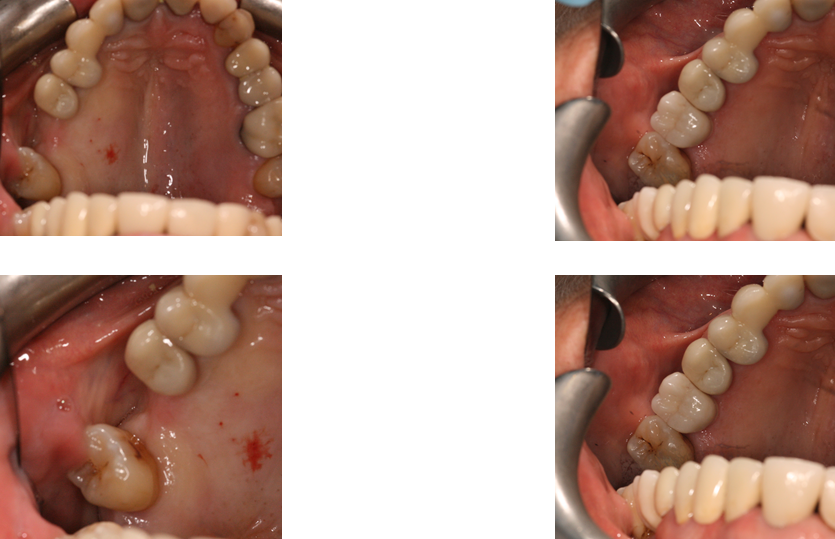

Here at Aesthetic Dental Zone we embrace new concepts, guided implant surgery provides a solution where doctors can plan an implant virtually, and then accurately place an implant in the safest, predictable and efficient manner.

With guided surgery, we place the implant for the best aesthetic result and can predict accurately how much room will be needed for the crown and for any veneered superstructure that may go over the abutment.

From a single missing tooth to an edentulous jaw. It aids your Doctor to diagnose, plan the treatment and place your implants based on restorative needs and surgical requirements.

Following an initial Implant Consultation and CBCT scan (3D Scan of your jaw) we can get to work on your specific Implant case.Guided Implant Surgery takes away the need to be too invasive when placing your dental implants.

It is extremely accurate, more comfortable and the healing time is reduced.Guided Implant Surgery is a state of the art technology, trust in us to make your implant process as simple and easy as possible.